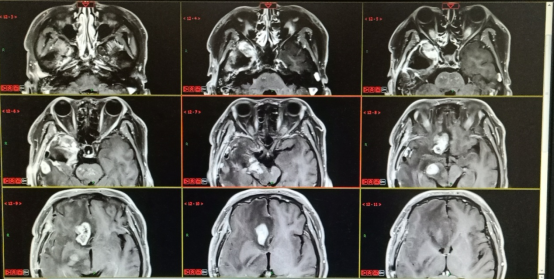

本次住院后给予患者心电监护、吸氧,住院期间患者左侧肢体肌力下降,约为3级,病出现头晕、头痛,恶心、呕吐症状,考虑患者病情加重,给予患者甘露醇125ml q8h iv,症状未见明显好转后,加用甲泼尼龙500mg qd iv,应用后患者头晕、头痛、恶心、呕吐症状缓解,但患者左侧肢体肌力未见好转,并出现饮水及饮食呛咳,于2021年1月16日给予患者贝伐珠单抗注射液700mg st iv,目前患者自述较之前精神好转。

2020.12.08三门峡市中心医院:右侧颞叶胶质瘤术后改变,病变范围较前增大,新见脑桥、右侧额叶强化,考虑肿瘤复发可能。

2021.01.08三门峡市中心医院:右侧颞叶胶质瘤术后改变,右额叶病灶较前增多,原脑干、右侧额叶病灶较前体积增大,考虑肿瘤进展。